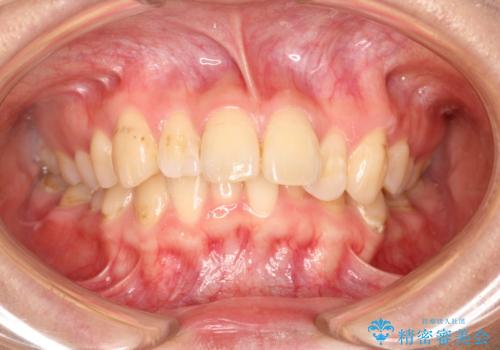

前歯の突出、深い噛み合わせ、ガタつきをマウスピース矯正(インビザライン)で治療した症例

- 初診時には上顎前歯の突出、前歯部の深いかみ合わせ、叢生が見られる状態でした。